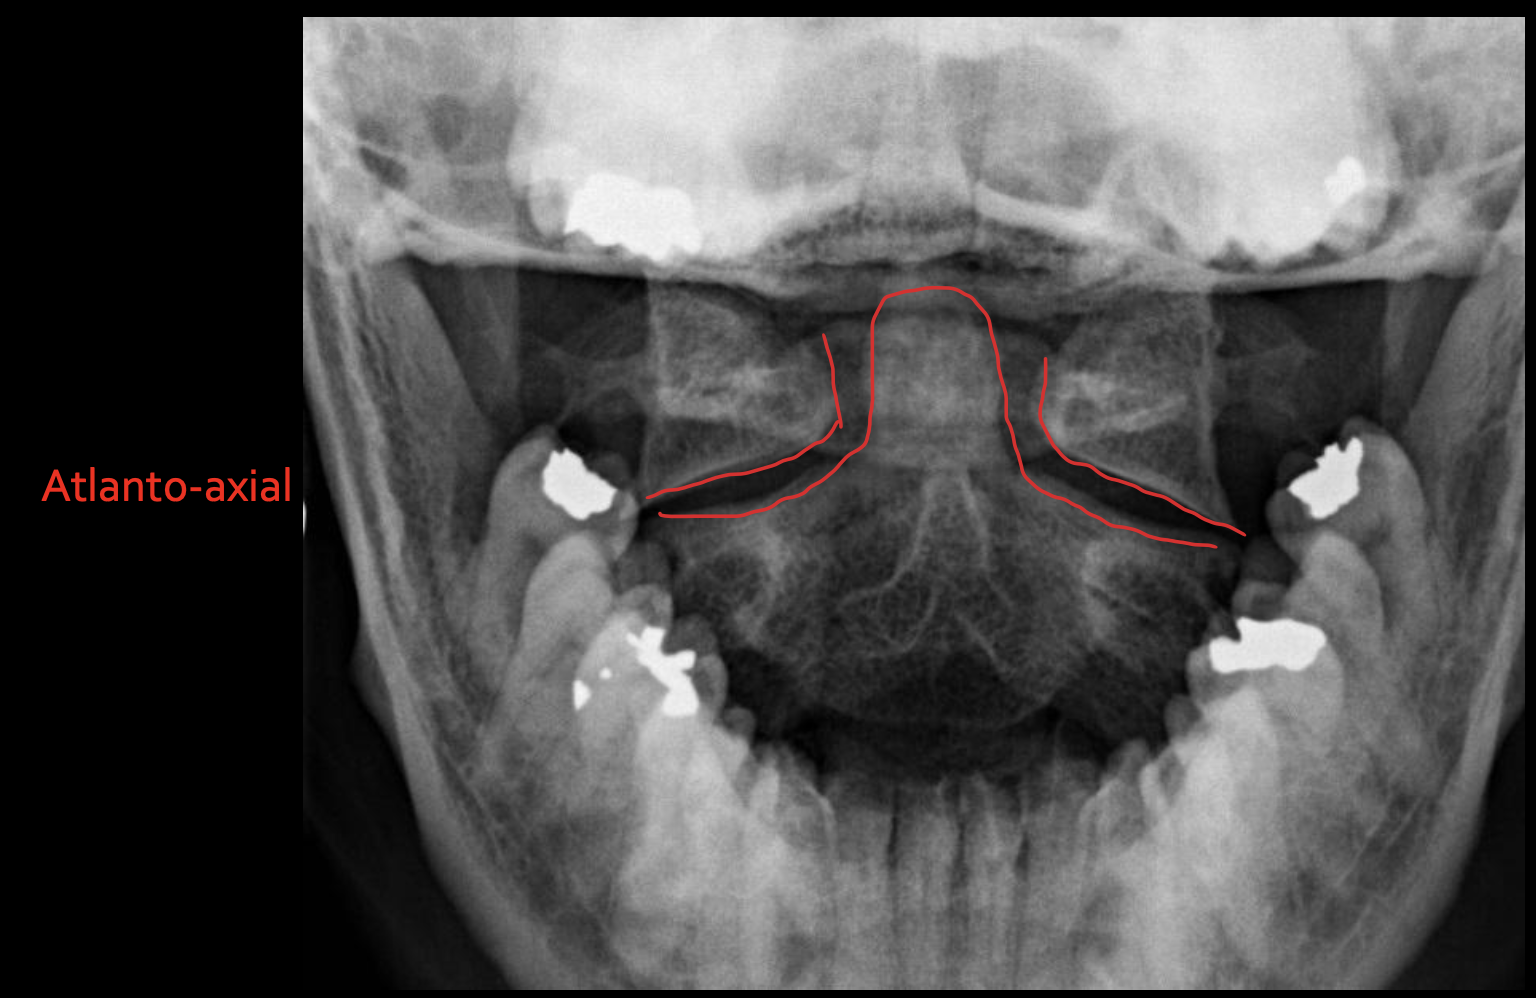

寰枢关节

Atlanto-axial